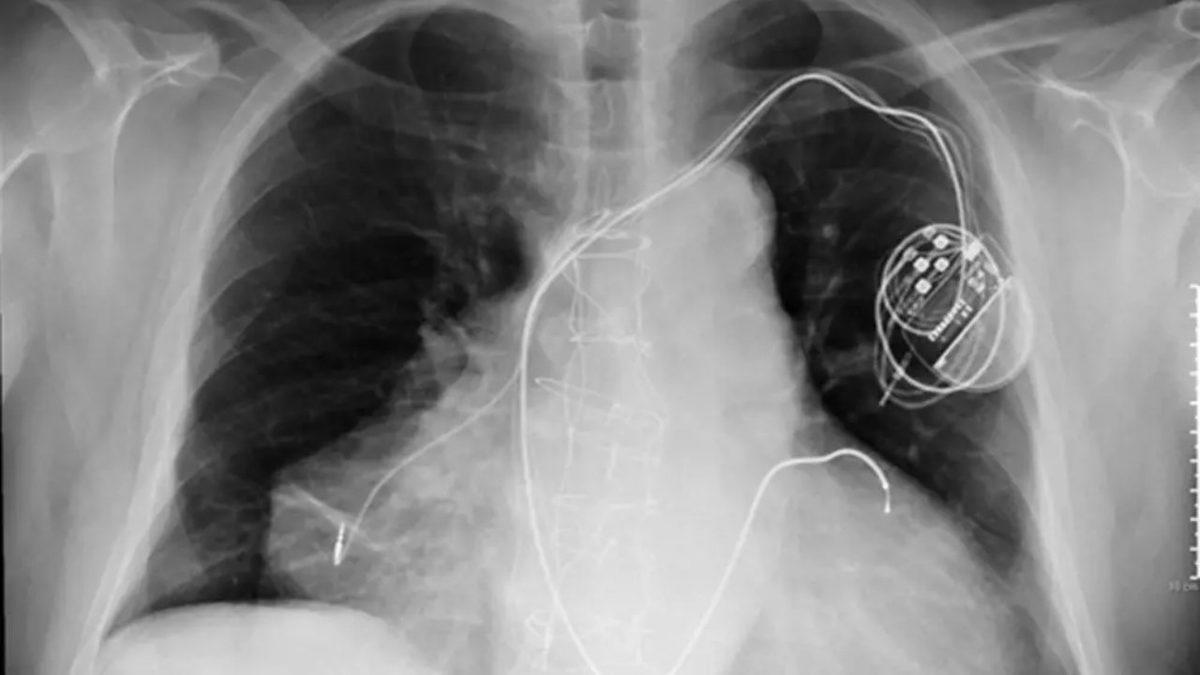

Ancak doktorlar, hastanın şikâyetinin neyden kaynaklandığını tespit etmeye çalışırken oldukça şaşırtıcı bir şeyle karşılaşıyor. Adamın 1 değil, 2 kalbi var!

Bu adam nefes darlığından henüz muzdarip olmadan birkaç yıl önce, yeni bir organın hastalıklı bir organla eşleştirildiği heterotopik kalp nakli olarak bilinen bir prosedür geçiriyor.

Böylece vücudunda 1 değil 2 kalp yer alıyor.